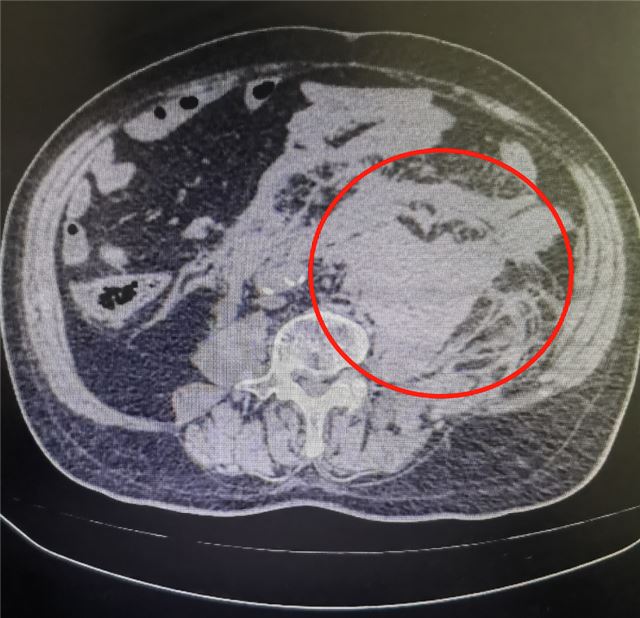

到达时,急诊时已经血压骤降(收缩压仅70mmHg),并再次陷入意识障碍,值班医生通过绿色通道迅速完善CT检查,准确判断为“腹主动脉瘤破裂出血”。

患者以最快速度剖腹探查到出血情况。术中显示,患者腹主动脉瘤体直径约达8cm,已破入后腹膜,局部形成巨大血肿。

动脉瘤破裂出血,后腹膜形成巨大血肿。

“必须立刻阻断瘤体近远端!”主刀医生沉着指挥,团队精准分离瘤体周围粘连组织,阻断血管,清除后腹膜血肿,再重建血管。2个半小时后,患者血压逐步回升,生命体征趋于平稳,手术顺利结束。